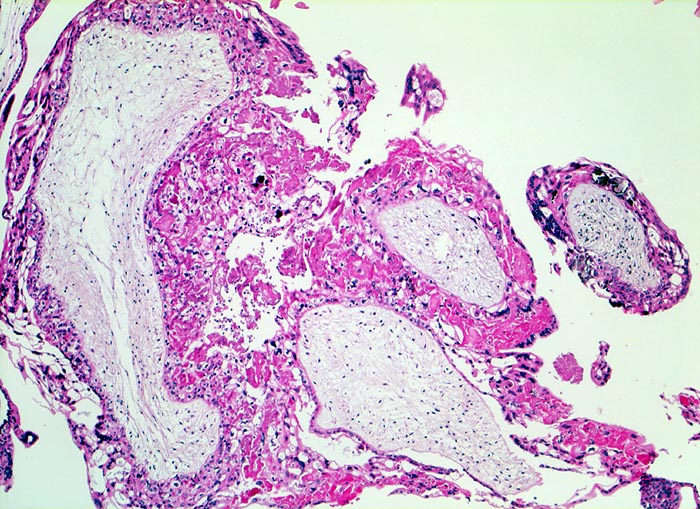

PathoPic ID 5251 - Blasenmole

Blasenmole

angeboren /genetisch/Missbildung

Abortmaterial

Paidopathologie

Gefässfreie blasig aufgetriebene Villi bedeckt von zirkulär proliferiertem Trophoblastepithel.

beta HCG Level von 150'000 mIU/mL. Uterus zu gross für das Gestationsalter von 10 Wochen. Arterielle Hypertonie.

Histologie

50